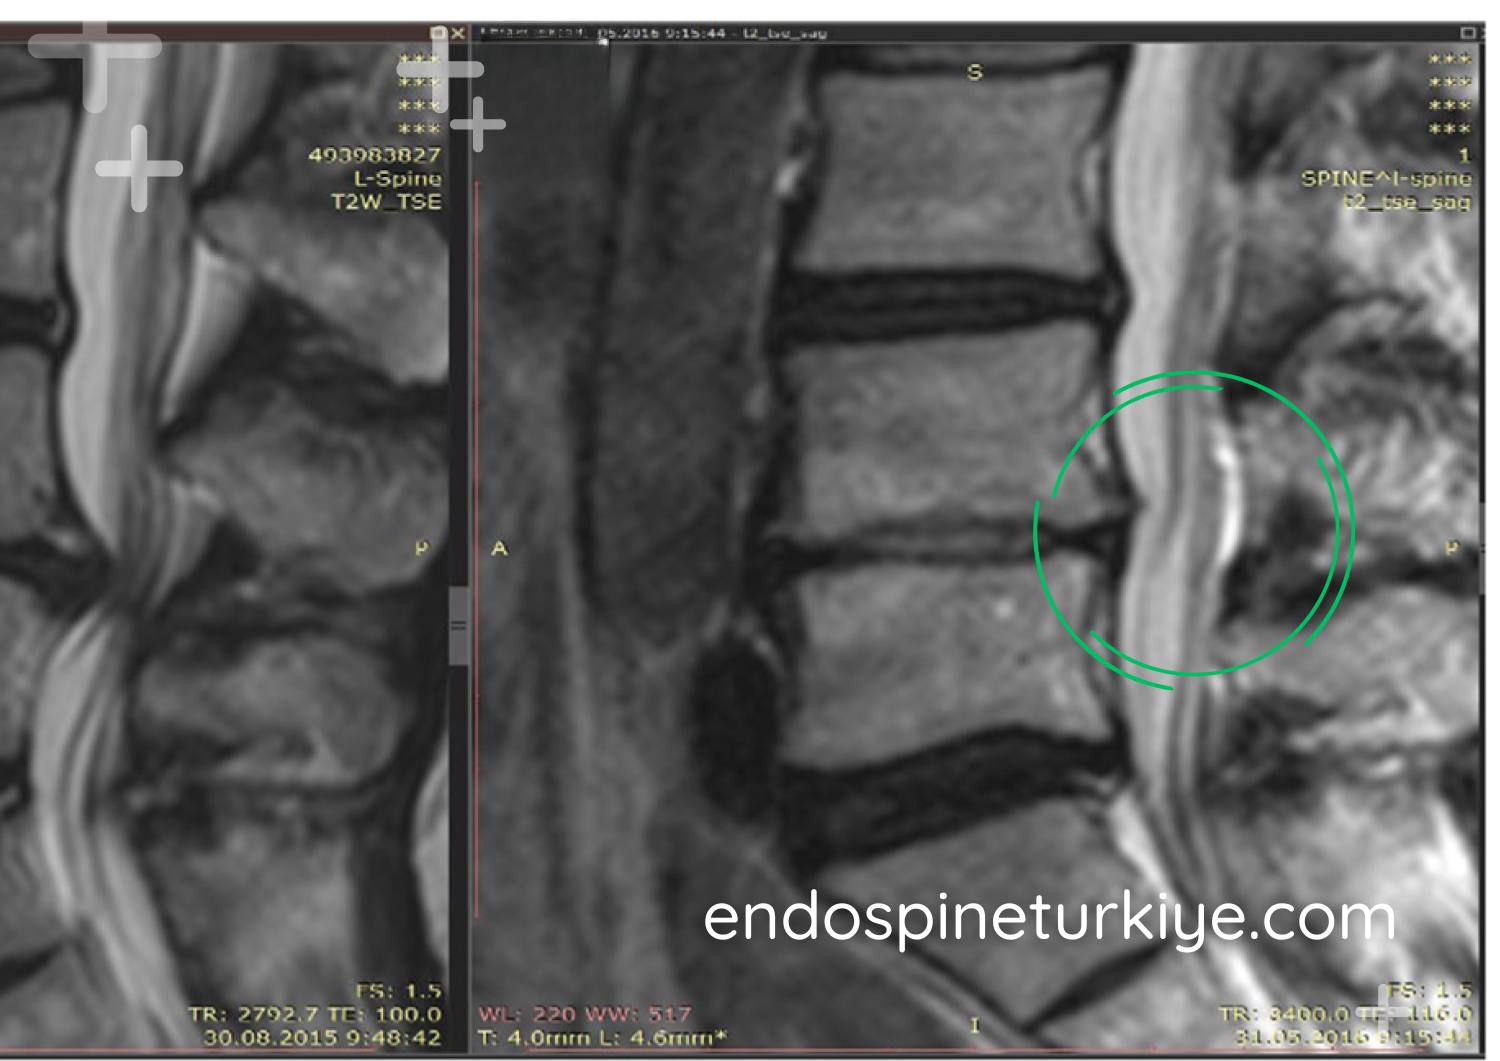

Bel Fıtığı Ameliyatı Öncesi ve Sonrası

Tedavi Sonrası

Tedavi Sonrası

MR görüntülerinde endoskopik bel fıtığı ameliyatı öncesi ve sonrası karşılaştırma